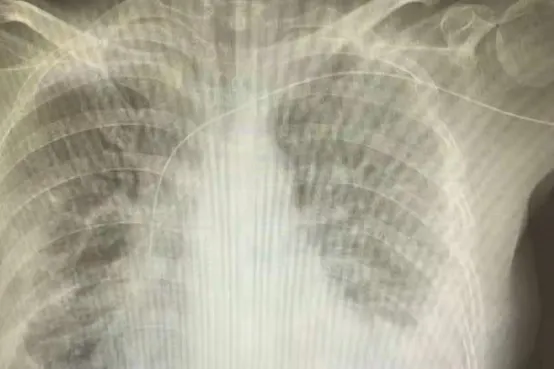

目前定位的方法有:置管后胸部X线、心脏超声、CT检查等。

虽然传统的X胸片是确定导管尖端位置的金标准,但无法实时定位,一旦发生导管异位,必然增加调整时感染几率以及调整后摄片的医疗费用,加大放射线对患者的危害。

“腔内心电图实时定位技术”则是通过特制的心电导联线连接PICC导管导丝和心电监护仪,观察置管过程中P波的特征性改变,来判断导管尖端是否达到CAJ位置。

图 | 导管在腔内不同深度部位的心电图变化